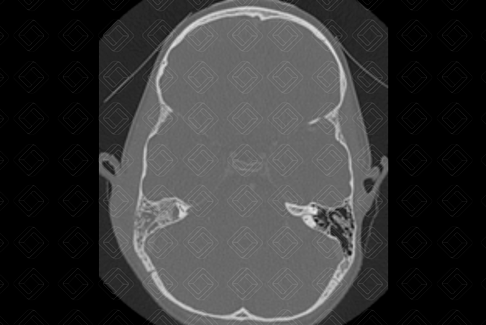

Descrição das figuras: Tomografia computadorizada das mastoides com contraste venoso. Observa-se no plano axial com filtro ósseo o preenchimento das células mastoideas à direita. As células mastoideas à esquerda encontram-se normoaeradas. Há ainda presença de coleção no ouvido externo à direita (setas vermelhas). Os planos axial e coronal caracterizam um quadro de otomastoidite à direita.

Mastoidite aguda: Trata-se da infecção das células mastoideas, representando a complicação mais comum das otites. Deve ser realizada com contraste venoso, para afastar possíveis complicações como coleções, trombose de seios venosos, erosões ósseas, osteomielites de base do crânio, abscessos cerebrais, meningite e outras

• Tomografia computadorizada das mastoides: O bserva-se preenchimento das células mastoides, com erosão dos septos. Deve ser realizada após a administração do contraste venoso para afastar complicações, como coleções, trombose de seios durais, abscessos cerebrais, osteomielite, erosões ósseas e outros;